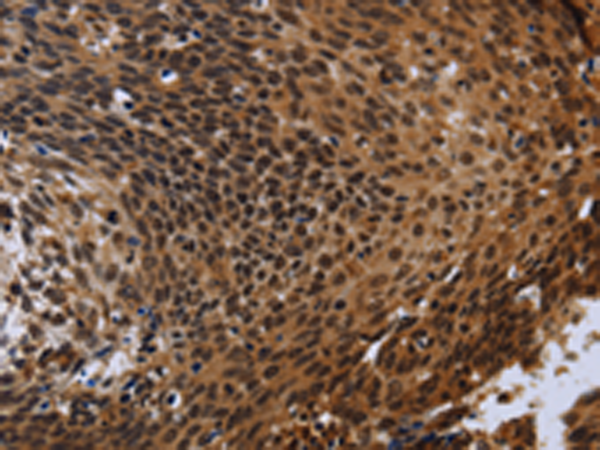

分类: 科研抗体货号: P01441别名: RNMX; HNRPG; HNRNPG; RBMXP1; RBMXRT; hnRNP-G应用: WB,IHC反应种属: Human, Mouse, Rat